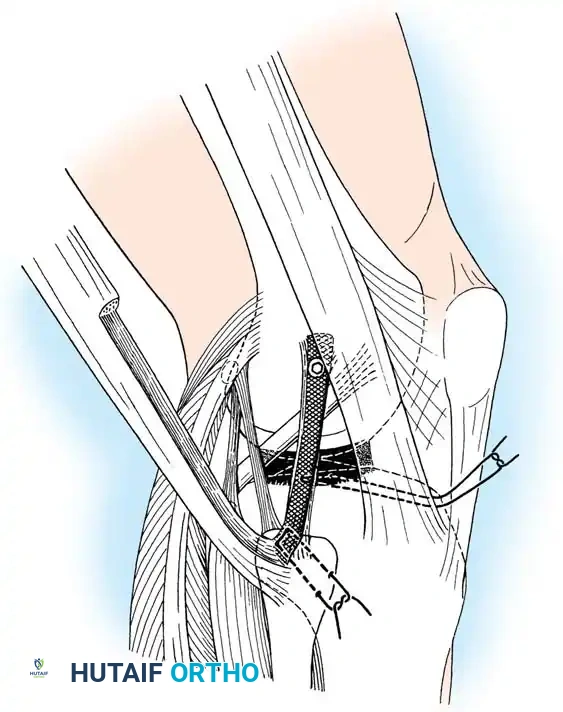

Lateral Collateral and Posterolateral Corner (PLC) Repair

Lateral-sided injuries are notoriously unforgiving and rarely heal with conservative management due to the inherent varus alignment of the lower extremity during the normal gait cycle.

A curvilinear incision is made over the lateral aspect of the knee, incorporating the iliotibial band and the biceps femoris. The common peroneal nerve must be identified, neurolysed, and protected with a vessel loop throughout the procedure.

Image

The LCL, popliteus tendon, and popliteofibular ligament are systematically evaluated. Avulsions from the fibular head are common.

Deep capsular tears are repaired with interrupted sutures. If the LCL or popliteus is avulsed from the lateral femoral epicondyle, anatomical footprints are identified, and the structures are repaired using suture anchors. Tensioning must be performed with the knee in 30 degrees of flexion and neutral rotation.

In cases where the native tissue is non-viable or the injury is subacute, an anatomical posterolateral corner reconstruction using an autograft or allograft (e.g., Achilles or semitendinosus) is mandated. The graft is routed to recreate the LCL and popliteofibular ligament.

Robust fixation is achieved using interference screws or screw-and-washer constructs in the fibular head and lateral femoral condyle. The biomechanical integrity of the construct is verified by taking the knee through a full range of motion, ensuring no impingement or laxity.